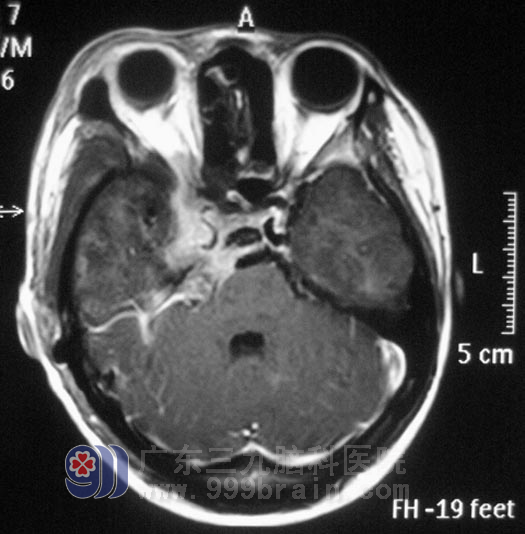

小李在2008年高考那年,出现右眼视力下降,以为是高负荷的复习迎考,造成视力出现问题。一年前右耳听力开始进行性下降,前十多天又出现了右耳失聪,外院行头颅MR检查提示:右侧眶内、中颅窝底、岩斜区占位,病变大小4.98cm×3.34cm×2.62cm,主要位于中颅窝,小部分累及后颅窝,脑干受压。

广东三九脑科医院综合神经外科 鲁明主任查阅影像资料发现:肿瘤侵润海绵窦,颅内外沟通,经CT检查见蝶骨及斜坡右侧、右侧颞骨岩部、额骨底部右侧骨质异常,经耳鼻喉科活检排除鼻咽癌。